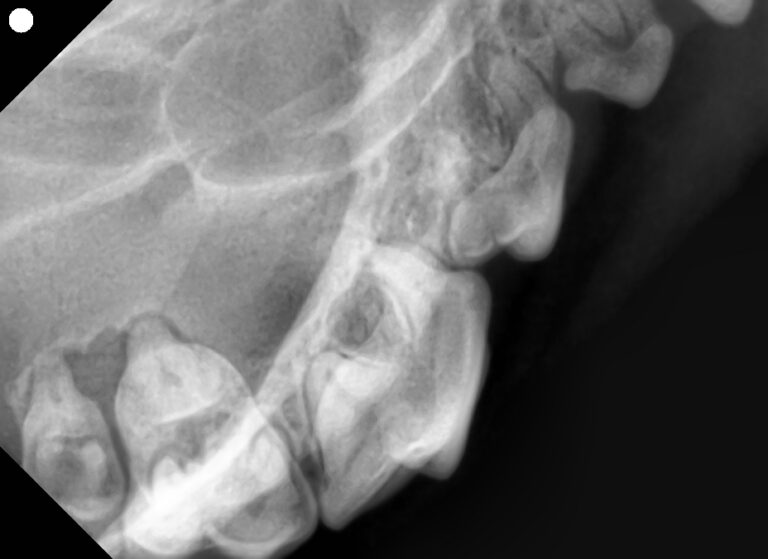

歯石除去